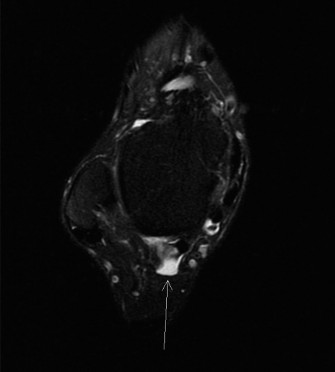

A 60-year-old male presents noting left foot pain of over a year’s duration. He was originally diagnosed with…

A 60-year-old female presents with a chief complaint of an intermittently painful mass on the medial border o…